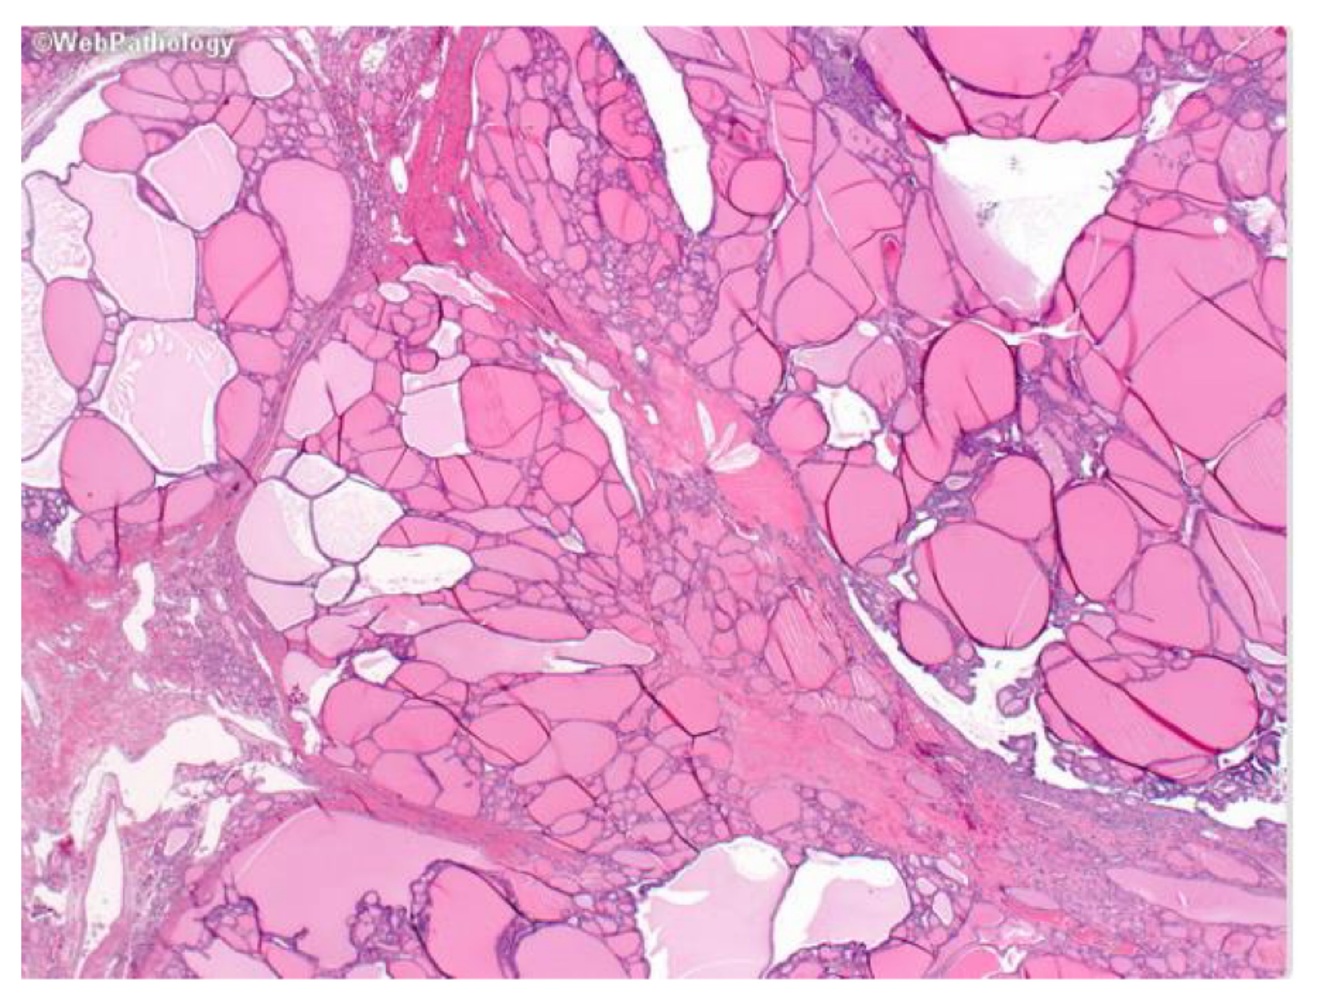

Thyroid tissue ;

Define the symbol and identify the stain used

A